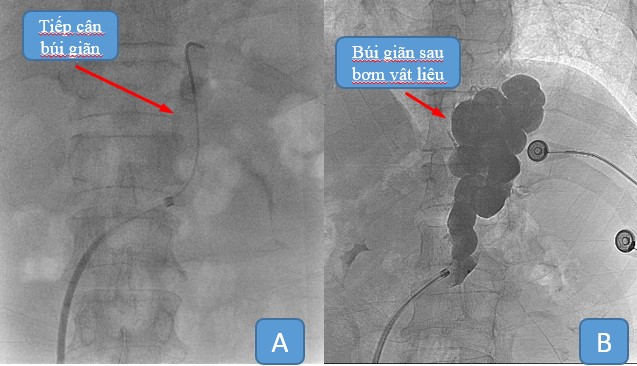

Kỹ thuật xâm lấn tối thiểu, chỉ cần can thiệp qua một lỗ chọc tại TM đùi, sau đó luồn dụng cụ dưới hướng dẫn của máy chụp mạch số hóa xóa nền (DSA) vào TM chủ dưới, tiếp cận shunt vị – thận, thả dù tắc mạch (Amplatzer plug), tắc shunt vị thận, tiếp cận búi giãn bơm vật liệu tắc mạch vào trong.

Hình 2: Tiếp cận búi giãn (A) và bơm vật liệu tắc mạch ngược dòng (B)

Trường hợp shunt vị thận lớn việc tắc shunt bằng plug bị hạn chế có thể kết hợp cả hai kĩ thuật xuôi dòng (trình bày ở bài khác) và phương pháp đi ngược dòng.